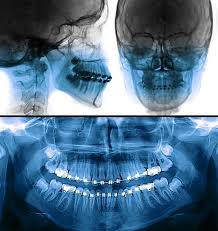

Panoramic Taken On Our Office On A 10 Year Old Child Showing Permanents As Well As Primary Teeth Unerupted Dental Treatment Dental Clinic Dental